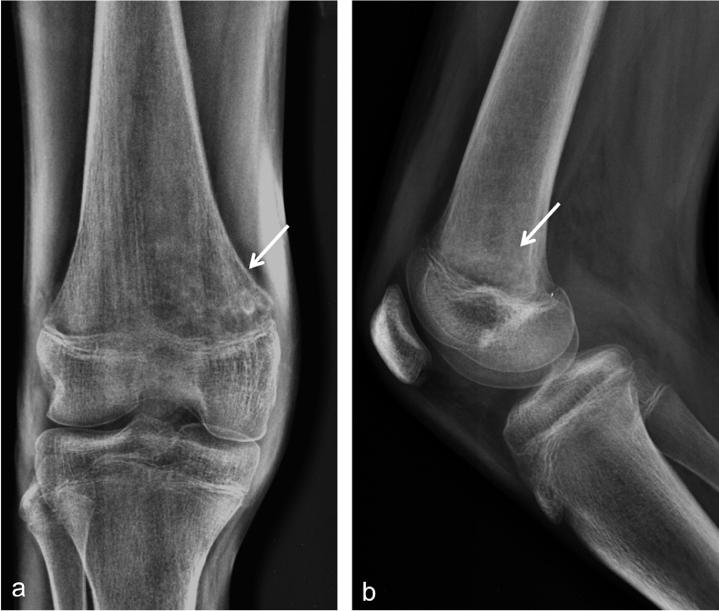

Magnetic resonance imaging (MRI) findings of acute osteomyelitis vary from non-specific bone marrow edema to more reliable signs such as bone destruction, periosteal reaction, and sequestrum. In some cases, imaging features could overlap with other conditions such as trauma and bone tumors. Intra and extramedullary fat globules are a helpful MRI marker for osteomyelitis, as shown in the following case report. We report the MRI findings of a 15-year-old young man with distal femur osteomyelitis, associated with intra and extramedullary fat globules.We present the MRI features of the case and emphasize the importance of noting additional signs of osteomyelitis to make a precise diagnosis.

急性骨髓炎的磁共振成像(MRI)表现各异,从非特异性骨髓水肿到更具诊断价值的征象,如骨质破坏、骨膜反应和死骨形成。在某些情况下,影像学特征可能与其他疾病(如创伤和骨肿瘤)重叠。骨髓内和骨髓外脂肪球是诊断骨髓炎的一项有用的MRI指标,如下例报告所示。我们报告了一名15岁男性股骨远端骨髓炎患者的MRI表现,该患者伴有骨髓内和骨髓外脂肪球。我们展示了该病例的MRI特征,并强调了注意骨髓炎其他征象以做出准确诊断的重要性。